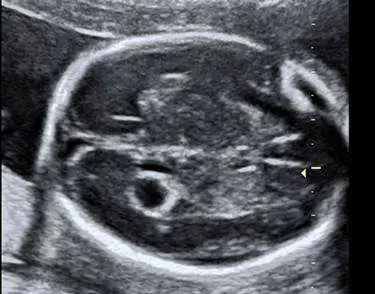

40 歲孕婦,G3P2 ,妊娠 22 週,接受檢查,結果如圖所示,則檢查之胎兒部位名稱為何?

產前超音波胎兒生物測量——雙頂徑(biparietal diameter, BPD)標準切面辨識。妊娠 18–22 週的第二孕期系統性超音波掃描,必須辨識胎兒各解剖部位的標準切面,此題考的是胎兒頭部(head)橫切面的標準 BPD 平面。

本圖為產科超音波影像,呈現胎兒頭部的標準橫切面(transverse/axial plane):

- 顱骨輪廓:影像中可見完整的橢圓形強回聲(hyperechoic)顱骨骨板,形成特徵性的「蛋形」外觀,代表完整的顱穹窿(cranial vault)。

- 大腦鐮(falx cerebri):中線可見一條線狀強回聲結構,將左右大腦半球分隔,稱為大腦鐮(falx cerebri),即正常的中線結構(midline echo)。

- 視丘(thalami):中線兩旁各有一個低回聲的卵圓形結構,即左右視丘(paired thalami);兩側視丘之間的低回聲縫隙為第三腦室(third ventricle)。

- 透明隔腔(cavum septum pellucidum, CSP):在視丘前方可見「框狀」(box-like)的低回聲空腔,即透明隔腔,這是確認正確切面的重要解剖標記。

- 黃色箭頭標記:影像右側可見黃色三角形箭頭(arrowhead),指向顱骨外緣,為 BPD